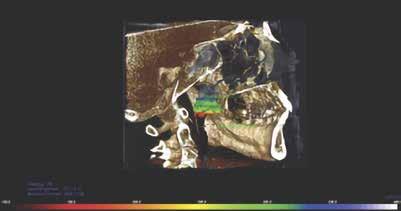

A páciens 3D CBCT lágy szövet renderelése. Szagittális CBCT-felvétel a csontszövetekről és a légutakról.

Az ízületek háromdimenziós képalkotása a condylusok és a fossa osteogenetikus átalakulását mutatta ki, amely az ízületek hosszú távú terhelésére utal (4–5. ábra)

4. ábra: A CBCT-vizsgálat 3 dimenziós információkat nyújtott a kondilusokról.

5. ábra: Az ízületek 3 dimenziós képalkotása a kondilusok és a fossa oszteogén átalakulását mutatja, amely az ízületek hosszú távú terhelésére utal.